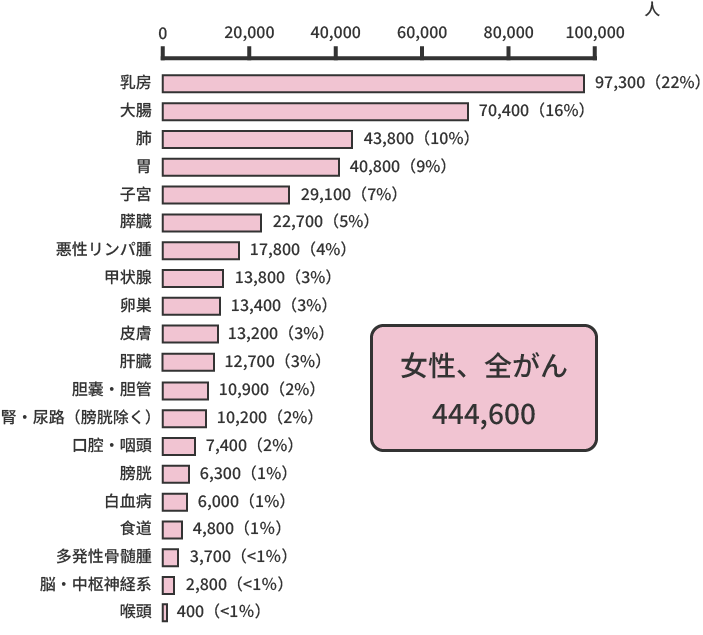

また、同じく2021年のデータによると、がんによる死亡者の数は、約37万8,600人(男性約21万8,900人、女性約15万9,700人)と推計されています。部位別でみると、男性では肺がん(24%)が最も多く、次いで大腸がん(13%)、胃がん(12%)、膵臓がん(8%)、肝臓がん(7%)の順、女性では大腸がん(16%)が最も多く、肺がん(14%)、膵臓がん(12%)、乳がん(10%)、胃がん(9%)と続きます。

部位別予測がん罹患数(2021年)

部位別のがん死亡者数(2020年)